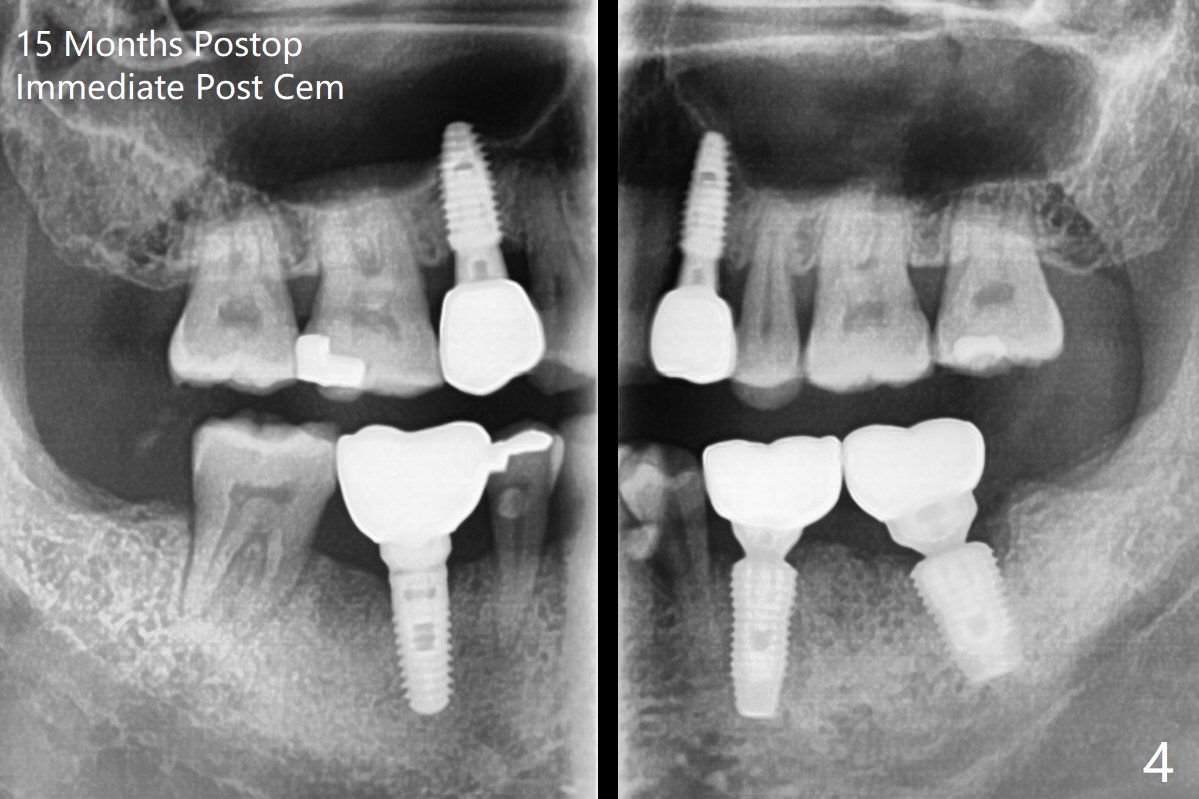

A 54-year-old man with bruxism requests treatment at #4 and 12 with buccal fistulae (Fig.1-3). Due to large defects, a large, but short implants (5x7.3 mm) will be used for primary stability. PRF membranes (x4) and liquid (x1 for sticky bone) will be prepared for sinus lift and buccal defect repair. Guided surgery will be utilized to prevent poor trajectory at #18 and 19 (Fig.1). The result turns out to be good (Fig.4).